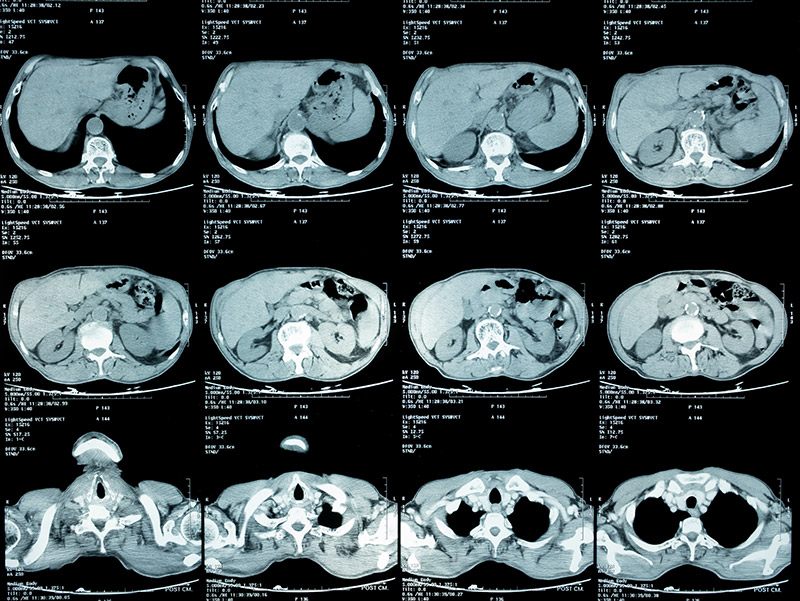

健康診断で再検査を言われ、精密検査をした結果、肺癌のステージⅣと言われました。その時は、もう何を言われたのか覚えてないですし、本当に頭が真っ白になりました。それまで、何気なく過ごしていた日常が全て失われ、何もかも嫌になりました。

それでも家族の支えもあり、少しずつ治療に前向きになり、抗がん剤治療などを受けましたが、残念ながら効果はありませんでした。副作用が強く、心も体も限界で抗がん剤治療をするくらいなら、もうステージⅣの悪性腫瘍が改善小さくなった画像を見て涙が止まりませんでした。死んでもいいと思っていました。

そんな時に私の友人から紹介され、松田先生に藁にもすがる思いで治療をお願いしました。私自身が治ることに諦めていましたが、松田先生は真摯に話を聞いてくれて、一生懸命治療をしてくれました。6ヶ月が経過した写真を見た時に、私でもわかるくらいにガンが小さくなっているのがわかりました。病院の先生の説明を聞きながら、涙を止まらなかったのを今でも覚えています。